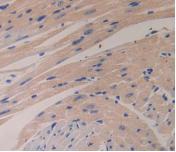

Polyclonal Antibody to Glucagon (GCG) (PAB266Mu01)

| Валидировано для | IHC WB Иммуногистохимия; Вестерн-блоттинг |

| Рекомендуемые разведения | WB: 0.5-2 мкг/мл; IHC: 5-20 мкг/мл; ICC: 5-20 мкг/мл; Оптимальное разведение определяется конечным потребителем |